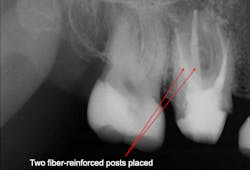

Because of the controversy and confusion about whether posts increase the strength of endodontically treated teeth, our research organization tested that subject. The results are available in the May 2004 issue of Clinicians Report (CR). Research showed that properly placed posts of any type available at the time increased the strength of endodontically treated teeth. Therefore, set that controversy aside. Posts strengthen teeth despite some contrary reports in the literature (figures 1 and 2).When should we use posts?

What are the characteristics of fiber-reinforced composite posts? They have flexibility, which results in fewer cracked teeth when patients suffer a forceful blow to the tooth. The research shows these posts have slightly less strength than strong metal posts, but that is good in this case. If the tooth is subjected to a blow, the crown usually comes off instead of the tooth cracking vertically. Fiber-reinforced posts are very simple to place and require only a few minutes when using an organized clinical procedure. When properly placed, these posts appear to provide near optimum characteristics after years of use.